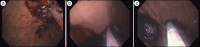

Figure 1.

(a) Outlining the lesion with cautery. (b) Mucosotomy. (c) Submucosal tunneling.